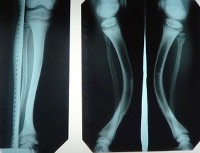

Рентгенологически при фосфат-диабете определяются классические признаки рахита – деформации костей голеней, коленных и тазобедренных суставов, наличие остеопороза (в некоторых случаях может возникать локальный остеосклероз) и остеомаляций. Изменена структура костей – кортикальный слой утолщается, трабекулярный рисунок становится более грубым, диафизы расширены. Нередко костный рентгенологический возраст при фосфат-диабете значительно отстает от фактического, что говорит о задержке развития скелета. Современная генетика позволяет диагностировать практически все типы этого заболевания, как правило, используется метод прямого секвенирования ассоциированных с патологией генов. В некоторых случаях указать на генетическую природу фосфат-диабета может изучение наследственного анамнеза больного.

- ренгенологические рахитоподобные изменения костей — широкие диафизы с утолщением кортикального слоя, грубый рисунок трабекул, остеопороз, вагусная деформация нижних конечностей, запаздывание формирования скелета; общее содержание кальция в скелете повышено.

- рентгенологически выявляются тяжелые рахитические изменения в зонах роста длинных трубчатых костей, истончение кортикального слоя, склонность к остеопорозу. Нет изменения КОС, содержания остаточно азота, но резко снижена концентрация l,25(OH)2D3 в крови.

- рентгенологически выявляются рахитические изменения разной степени.

При рентгенологическом исследовании костей обнаруживают широкий метафиз, утолщение кортикального слоя трубчатых костей. Содержание кальция в костях, как правило, повышено.